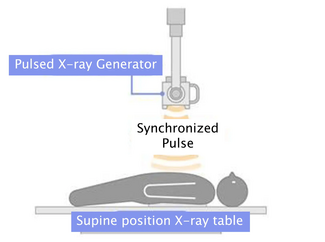

For years, we have accepted critical limb ischemia (CLI) as an end result of peripheral arterial disease (PAD). Recently, we have noticed an influx of patients transforming from PAD into CLI over the course of years. One should stop and think about the course of transformation from PAD to CLI, and if there is any indication that these transformations occur during a time when the patient is no longer a claudicant, but not yet technically diagnosed as CLI. What do we call such patients? The most realistic  description, in my opinion, is pre-CLI.

Figure 1 is an example of a patient referred to as advanced Rutherford 3 claudication, occasionally referred to as Rutherford 3a-b. But the same patient shows an anatomical obstruction in the arterial supply of the lower extremity consistent with CLI anatomical distribution. However, this patient presented with symptoms consistent with claudication. Historically, we differentiated these patients by performing additional hemodynamic assessments such as toe brachial index (TBI), toe pressures, ankle pressures, etc. This specific patient presents with claudication with anatomical variations consistent with CLI and a hemodynamic assessment consistent with CLI. We are now faced with a therapeutic options dilemma between high-risk revascularization of either a tibial vascular bypass surgical repair or high-risk endovascular revascularization. At this point in time, there is no trial data to answer the question of why and how these patients should be treated. It has been observed, in the arena of CLI therapists, that the provision of early therapy to patients with this type of anatomy may prevent or delay the presentation of CLI. As we well know once CLI presents, especially advanced CLI of Rutherford stages 5 and 6, there is a high association with comorbidities and mortality.

Therefore, these patients with strong evidence of CLI by means of anatomy and hemodynamic measurements, but not strong evidence of clinical presentation in terms of symptoms, fall into the category between advanced claudication and technical CLI. It is  fair to say that this patient should be referred to as pre-CLI based on the fact they already have significant indications of CLI based on the anatomy and hemodynamic measurements.

Of course the issue of what should be done with such patients remains controversial. Also, as mentioned above, the lack of data continues to be a major barrier as well. But such patients are becoming more common than ever, as there is far more awareness of the seriousness and implication of CLI, and because more research is being done on such patients. Now that we are able to identify these patients, it is my opinion that they should be revascularized if they meet one of the following criteria:

- The patient presents as pre-CLI with symptoms of advanced PAD and anatomical disease consistent with CLI anatomy, such as advanced tibial disease.

- The patient presents with hemodynamic indications consistent with CLI disease.

The revascularization choice between endovascular intervention or vascular bypass should be determined based on the best option for the anatomy we are faced with.

In Figure 2, far more advanced anatomical disease can be seen, speaking volumes to the fact that a CLI diagnosis cannot be made by observation and physical assessment alone. This patient, at this point, has no feeling in the lower extremities, including the  feet. Therefore, this patient does not complain of any rest pain and is active. The question here is, what do we do with this type of patient? Again, this is a controversial issue, but a reality we face every day. Theoretically, we can extrapolate that some of these patients don’t have feeling secondary to diabetic neuropathy. Additionally, ischemic neuropathy caused by advanced and chronic lack of blood supply to the lower extremities may lead to some of these patients losing feeling in their feet.

Interestingly, not all of these patients will have a hemodynamic abnormality consistent with CLI, which could be due to multiple underlying causes. The most common is calcification of the tibial pedal vessels, which tend to cause elevated ankle-brachial indexes and other hemodynamic measurements such as TBIs.

Again, this leaves us with yet another major dilemma: patients with no active rest pain or claudication found to have angiographically determined advanced disease, as shown in Figure 3. What do we do with such patients? There is a significant split in opinion between operators on how such patients should be treated. Some would say leave it alone and observe until there is progression of symptoms. Some would say medical therapy alone is sufficient. Some would say definitely revascularization of some sort. My personal opinion has been to evaluate and assess each patient individually. In my practice, I have seen many such patients present with this type of anatomy; we have observed them over time and they tend to do well. However, with the sudden occurrence of any acute change, such as any trauma leading to skin breakdown or additional loss of a collateral for any reason (embolization, plaque rupture or acute thrombosis of a collateral), we see presentation of another devastating event: the cold foot. Development of  a cold foot quickly puts these patients in the critical category of acute CLI with high likelihood for need of amputation. This prevents an ethical dilemma. Should we have treated such patients earlier when they were stable, with no apparent urgency, and created some revascularization to the foot, leaving a backup system for the future? Would this have made a difference in patient outcome? Observational theory would say yes, but medicine requires data. We don’t yet have this data available to us now, at the time we need to make critical decisions for the best patient outcome.

In my opinion and in my current practice, I tend to look at these pre-CLI patients with the same binocular vision I use for CLI patients. Once the anatomical variation of CLI is present and any hemodynamic abnormality of CLI is present, regardless of the initial presentation, I believe these patients should have some form of revascularization. They should potentially be treated early and with the same aggressiveness with which we treat CLI patients today. Although we don’t have clinical trials to support my opinion at this time, I am hopeful we will in the near future. In the meantime, pre-CLI is a serious stage of advanced PAD and should be addressed as an urgent matter.